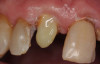

Case 1

A Class IN maxillary bicuspid was previously restored with a fiber post and an all-porcelain crown (Figure 1). The forces of the oral environment resulted in fracture of the fiber post and crown failure. The remaining fiber post in the root was removed, and anti-rotational areas were prepared for a cast post (Figure 2). A gold cast post was constructed at a dental laboratory, using an indirect technique (Figure 3). A porcelain-fused-to-metal (PFM) crown was constructed with a bevel finish to provide a ferrule and reduce forces on the post (Figure 4 and Figure 5).

Figure 4  The cast post was cemented.

Figure 4